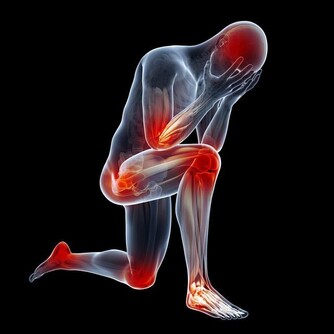

以下圖片來源weixin 4、強化肌肉 適量喝水能夠防止肌肉抽筋,潤滑身體關節。如果體內有足夠的水分,運動的強度可以更大、時間也可以更長,更晚感受到極限,這也有助於練出健美的身材。 5、滋養肌膚 一旦脫水,皮膚上細小的皺紋和紋理將會變深。水是天然的美容霜,喝水能為皮膚細胞補充水分,使它們更飽滿,讓人看起來更年輕。而且水分能夠去除肌膚上的污垢,改善血液循環,使肌膚煥發光彩。 如果在喝水時加上5種食物會有更多的益處哦。